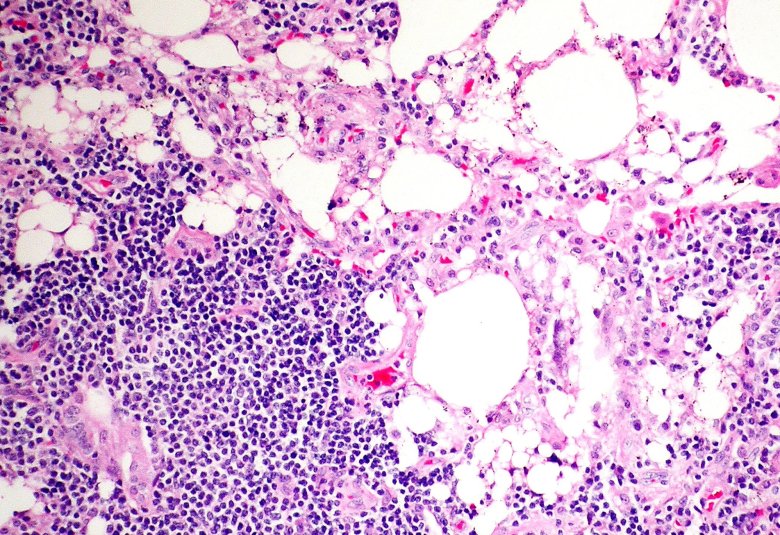

A yaws papilloma from a child living in a yaws endemic village in Papua New Guinea. These papilloma are often an early presentation of yaws and are teeming with bacteria.